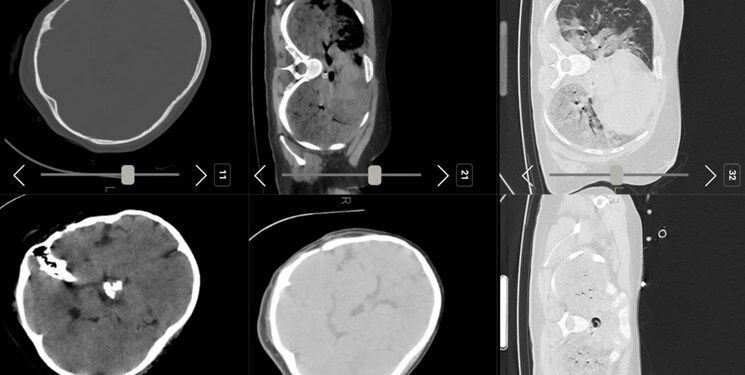

فارس: تصاویر سیتی اسکن مهسا امینی نشان می دهد او در سال های قبل جراحی سر داشته است

فارس نوشت: صبح امروز شبکه اینترنشنال عکسی از سی‌تی اسکن مرحوم مهسا امینی منتشر کرد و مدعی شد که «سی‌تی اسکن مهسا نشانگر شکستگی جمجمه، خون‌ریزی و ادم مغزی است»...متخصصان معتقدند بررسی‌های سی تی اسکن بیمارستان نشان می‌دهد هیچ شواهدی از ضربه به سر و خونریزی در این تصاویر به چشم نمی‌خورد.

با اینکه در ابتدا تصور می شد این تصاویر به مانند بسیاری از اخبار این رسانه جعلی باشد اما پیگیری های خبرنگار فارس از مراجع ذیربط نشان داد تصاویر سیتی اسکن منتشر شده مربوط به مرحوم #مهسا_امینی است.

برای بررسی علمی این موضوع با تعدادی از پزشکان مغز و اعصاب و رادیولوژیست گفت‌وگو کردیم تا به صورت علمی این موضوع را بررسی کنیم. این متخصصان معتقدند بررسی‌های سی تی اسکن بیمارستان نشان می‌دهد هیچ شواهدی از ضربه به سر و خونریزی در این تصاویر به چشم نمی‌خورد.

یک متخصص جراحی مغز و اعصاب به خبرنگار ما گفت: بررسی‌ها نشان می‌دهد که بیمار در گذشته جراحی در ناحیه سر انجام داده است اما براساس شواهد موجود از روی سی‌تی‌اسکن نمی‌توان فهمید که جراحی دقیقاً مربوط به چند سال قبل است. همچنین شواهد کرانیتومی فرونتوتمپورال قبلی همراه با آتروفی مختصر عضلانی و تغییرات بافت نرم در محل جراحی بیمار مشهود است.

یکی دیگر از پزشکان مغز و اعصاب نیز جراحی تومور بیمار را تایید می‌کند. به گفته این متخصص مغز و اعصاب متاسفانه برخی از افراد با دیدن تصاویر ناقص سی تی اسکن درفضای مجازی اقدام به اعلام نظر کرده‌اند اما واقعیت این است که در تصاویر کامل اثری از شکستگی نیست و این رسانه سعودی تصاویر را از زاویه‌ای منتشر کرده است که شکستگی به نظر برسد.